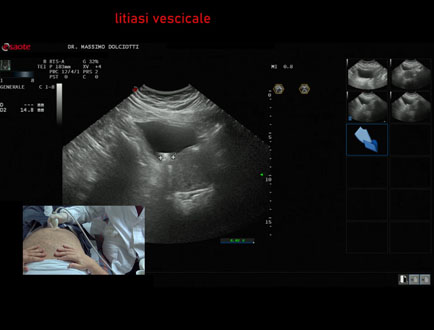

Ecografia del: 03/05/2025

Strumento: Esaote MyLab Eight

Sonda: Convex Multifrequenza 1-8 MHz

Età Paziente: M 74 anni

Motivazione dell'esame: follow up per diverticolo vescicale e calcoli, in soggetto con ipertrofia prostatica benigna

Commento all'esame: le immagini ed il video documentano la vescica, a buon riempimento e con presenza di grande diverticolo vescicale sulla parete laterale sinistra e al suo interno evidenza di multiple immagini iperecogene, mobili con il decubito da ricondurre a litiasi.

Conclusioni: grande diverticolo vescicale con litiasi (large bladder diverticulum with stones).